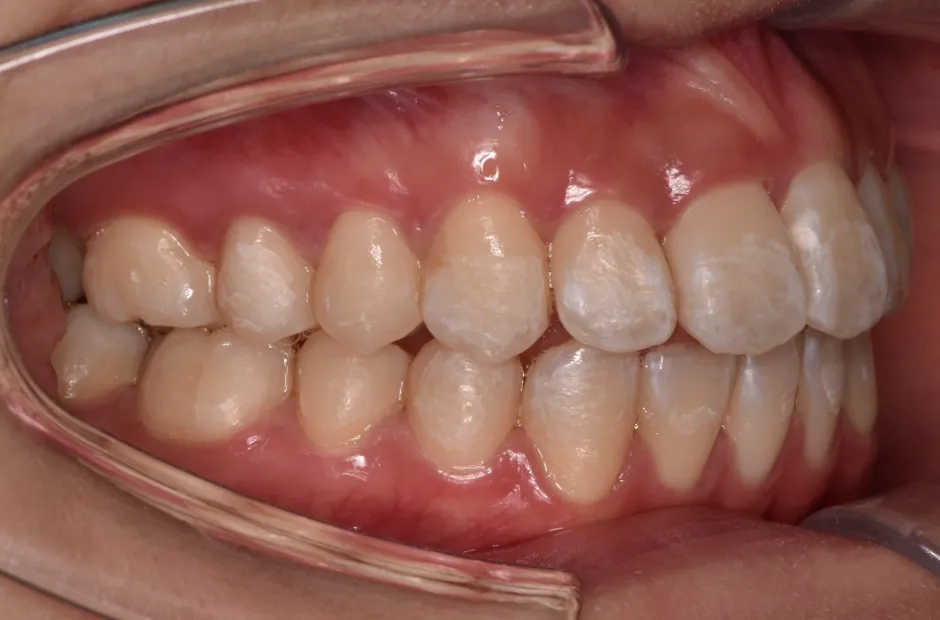

治療症例

ブラケット矯正

前歯部反対咬合

| 診断名・主訴 | 前歯部反対咬合 |

|---|---|

| 年齢・性別 | 14歳・男性 |

| 治療期間・回数 | 1年2か月 |

| 治療に用いた主な装置 | ブラケット矯正 |

| 抜歯部位 | なし |

| 治療費 | 60万円(税抜) |

| リスク・副作用 | 装置による違和感・疼痛・歯肉退縮・歯根吸収・虫歯のリスクなど |

治療前

治療中